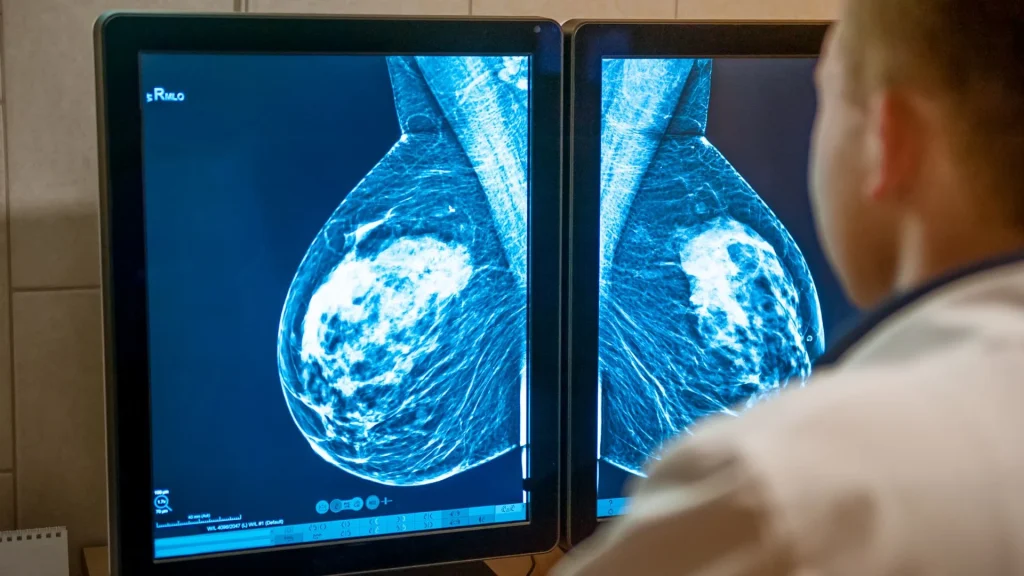

Teknologi 3D mammo atau tomosynthesis memisahkan jaringan payudara menjadi irisan tipis sehingga struktur tidak saling menutupi. Pemisahan ini membantu dokter melihat kelainan secara lebih spesifik tanpa artefak bayangan yang umum terjadi pada citra dua dimensi. Dengan gambaran yang lebih bersih, area yang sebelumnya tampak mencurigakan dapat dinilai ulang secara lebih objektif. Pendekatan ini secara langsung menurunkan kemungkinan interpretasi yang keliru.

Pada mammografi konvensional, tumpang tindih jaringan sering menghasilkan bayangan palsu yang terlihat seperti lesi. Tomosynthesis meminimalkan fenomena tersebut dengan menyajikan struktur secara berlapis. Hal ini membantu dokter membedakan apakah suatu daerah benar-benar merupakan kelainan atau hanya hasil penumpukan jaringan. Akurasi yang meningkat berkontribusi pada penurunan false positive.

Setiap irisan gambar memberikan definisi yang lebih baik terhadap batas dan bentuk kelainan. Lesi jinak yang sering tampak ambigu pada gambar 2D menjadi lebih mudah diidentifikasi sifatnya melalui visualisasi berlapis. Dengan informasi yang lebih lengkap, dokter dapat menilai temuan dengan tingkat keyakinan yang lebih tinggi. Penilaian presisi ini mengurangi rekomendasi pemeriksaan tambahan yang tidak diperlukan.